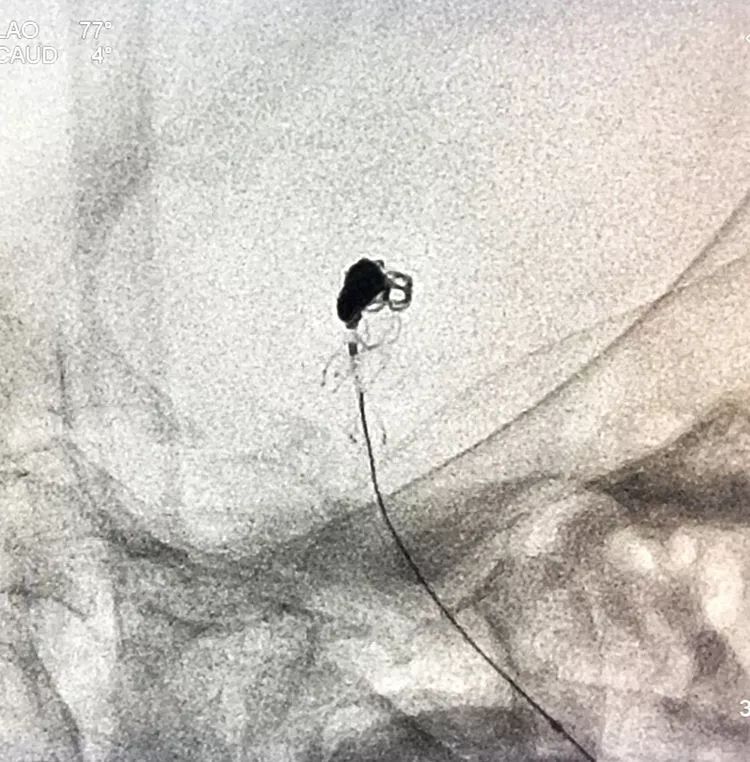

换用一根新的Echelon10微导管,头端塑成C型,以Arvigo14微导丝引导(先前的Sychro14微导丝的头端已经有损了),经LVIS支架内部接近瘤腔后部的死腔,但微导丝可以进入死腔,微导管头死活钻不进去,被LVIS支架的网丝挡住去路,怎么办?那就隔着渔网袜挠痒!

微导管头顶在支架网眼处,投送一枚1.5-2的小圈,一开始弹簧圈走行入载瘤动脉(支架)内,用扭具调整弹簧圈头端的行进方向,并随之微调微导管头的方向和张力,圈终于成功钻入死腔!